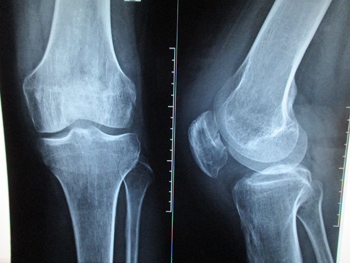

«Мама много лет работала поваром, социальным работником, но 13 лет назад случилась беда – после диагноза «фибросаркома» мама стала инвалидом второй группы. В настоящее время ситуация резко ухудшилась, и маме срочно нужна операция на правой голени с замещением дефекта индивидуальным модульным эндопротезом Mutars, производства Германии, потому что в Украине таких эндопротезов пока не делают. Прошу неравнодушных людей помочь собрать нужную сумму, для того чтобы моя мамочка, которой всего 49 лет, могла сама ходить, ведь сейчас она прикована к постели!», – рассказала Илона.